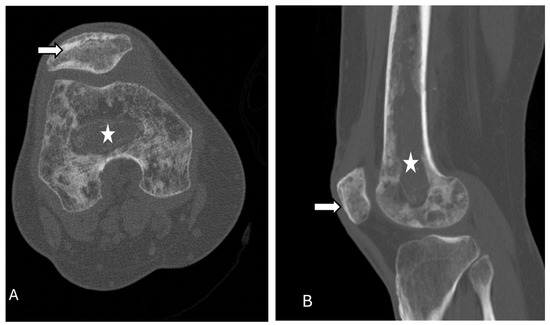

3.9. Osteomyletis of Patella